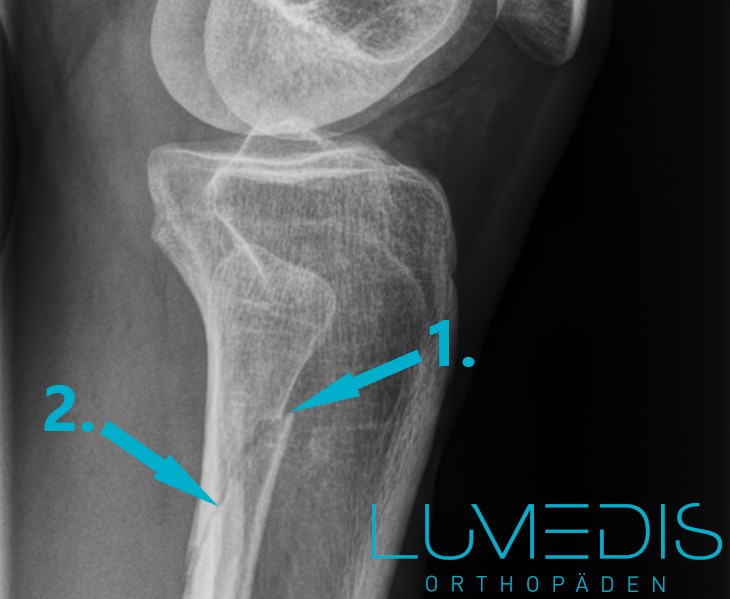

Das Röntgenbild stellt den Goldstandard in der Diagnostik von Knochenfrakturen dar.

Dabei lassen sich Knochenstrukturen im Röntgen besonders detailreich abbilden.

Sobald eine Frakturlinie im Bereich des Wadenbeins erkennbar ist, gilt die Diagnose als gesichert.

Zur besseren Beurteilbarkeit wird das Röntgen des Wadenbeins stets in zwei Ebenen durchgeführt.

Röntgenbild eines Wadenbeinbruchs von der Seite